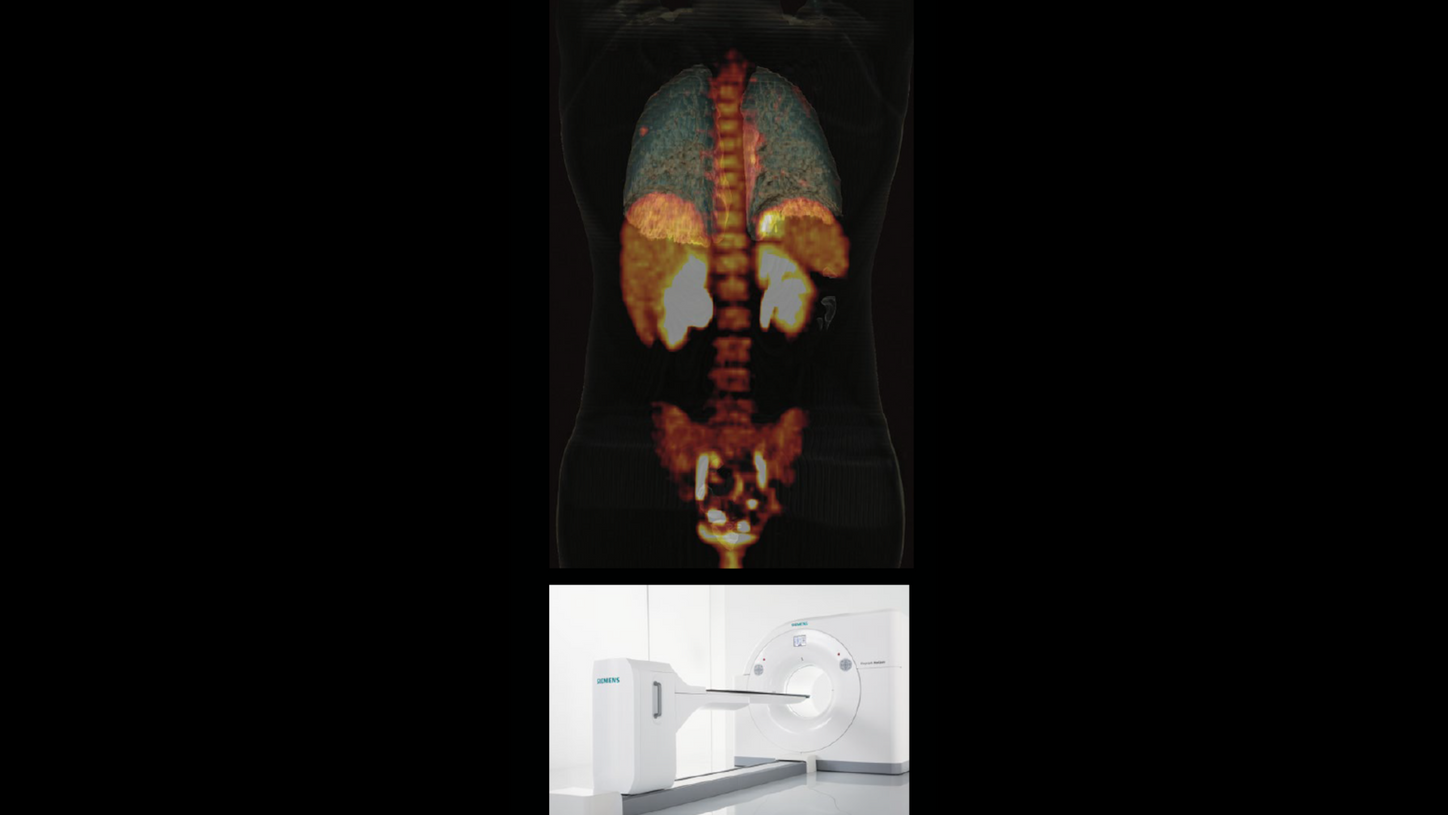

Biograph mCT is announced as the world’s first molecular computed tomography system and represents the evolution of integration in imaging. Biograph mCT is a combination of a state-of-the-art CT scanner with a high-performance PET system.

2013

Biograph mCT Flow is the first PET/CT system to move the patient through the gantry while continuously acquiring PET data.

2015

Biograph Horizon offers high-resolution imaging, advanced PET and CT technologies, and AI-powered workflows. Its compact design and simplified operations enable more healthcare providers to offer a higher standard of care to more patients.

Conti also speaks with particular pride about two projects: the first TOF PET/CT scanner from Siemens Healthineers, Biograph mCT, which was “a revolution in those years—a truly outstanding machine,” he says— and Biograph Vision Quadra total-body PET/CT. “It was an unusually fast project. Can you believe that it was done in about 1.5 years?”